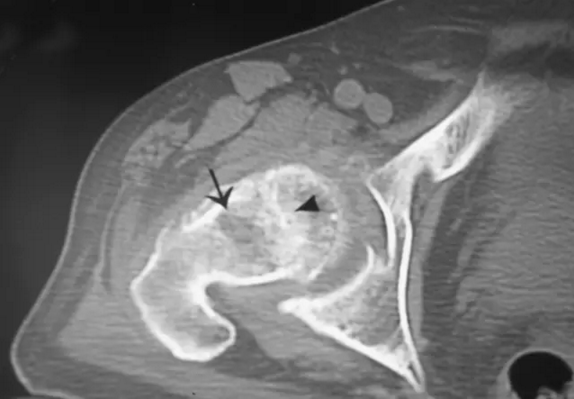

股骨头缺血坏死

对股骨头缺血坏死的患者CT显示中央小梁的聚集和变形。